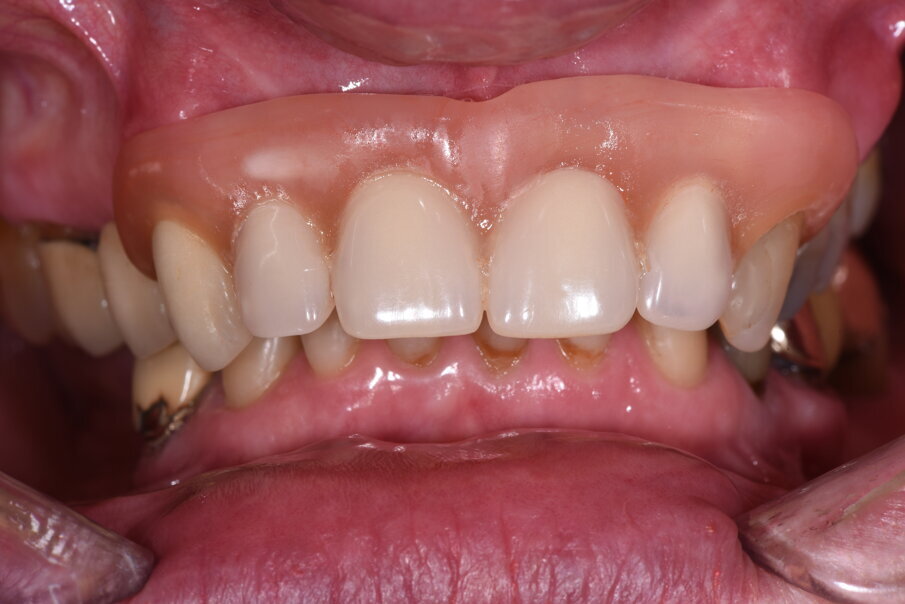

Fig. 1_Foto iniziale con il provvisorio rimovibile in posizione. La presenza di una flangia in resina consente un maggior supporto labiale.

Fig. 16_Il primo provvisorio eseguito in prematura e posizionato sull’intera arcata dentaria escludendo i secondi molari.